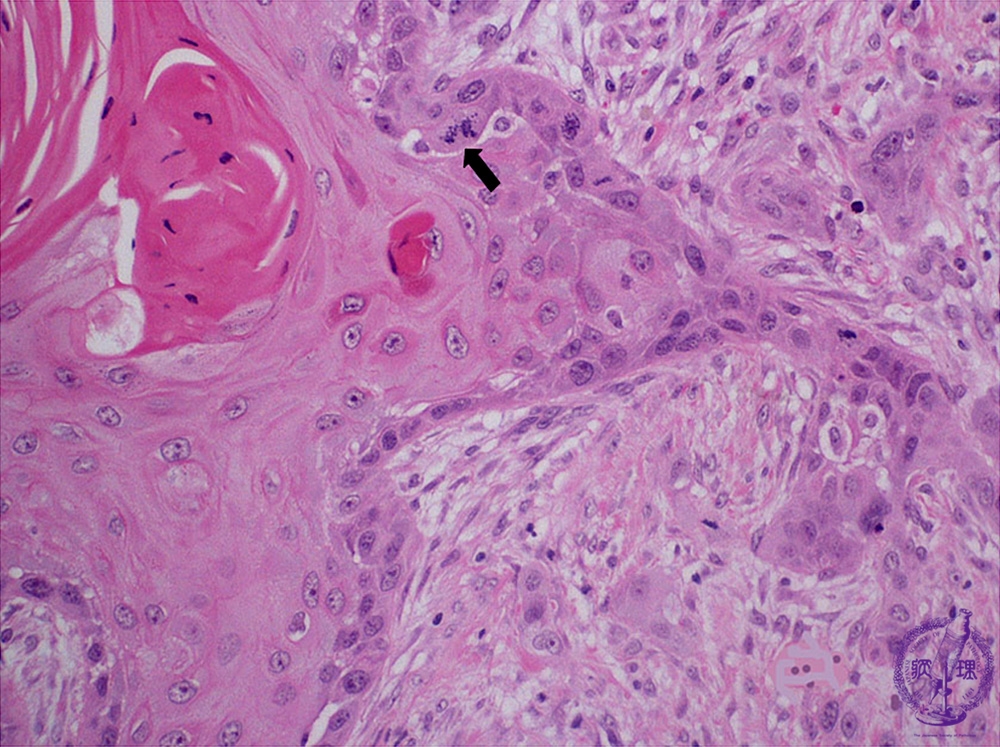

- ★(6)Oral cancer (Squamous cell carcinoma)

Microscopic finding (HE stain, high-power view):Despite exhibiting keratinization and recognizable stratified squamous cell epithelium architecture, there are characteristic features of cancer such as nuclear pleomorphism and atypical mitoses (arrow).